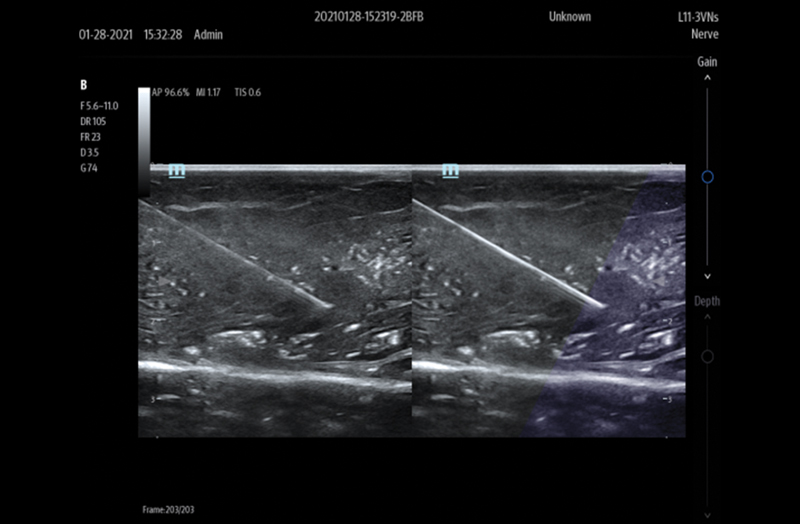

Advanced Technologies

Elevating Outcomes Through Innovation

Advanced Technologies

Needle Guidance